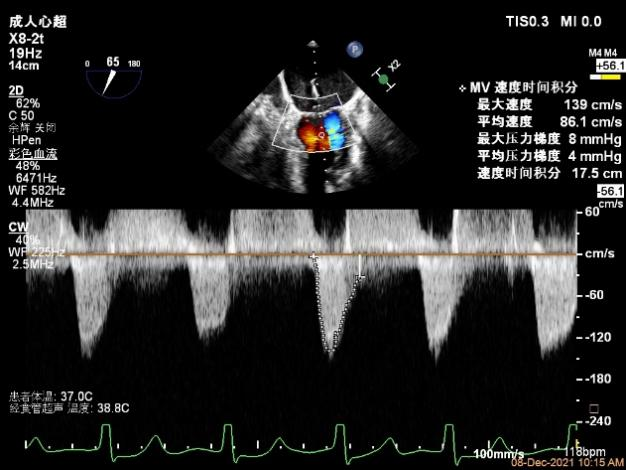

第一个夹子放置侯二尖瓣口平均跨瓣压差:4mmHg

肺静脉血流频谱恢复正向

x-plane验证前后叶抓捕后bond明显